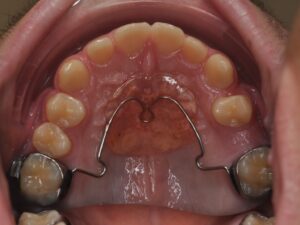

L'AXE DENTAIRE

Il correspond au maintien ou à la réouverture des espaces afin que les dents définitives puissent évoluer.

Les dents de lait sont souvent sous-estimées mais elles jouent un rôle primordial dans l’éruption des dents définitives. Il faut savoir que la nature n’aime pas le vide, une perte prématurée d’une « dent de lait » entrainerait un risque d’absence de place pour la « dent d’adulte ». Il peut donc être nécessaire de maintenir ou de rouvrir certains espaces.

Il s’agit de la mastication, la respiration, la posture linguale, les habitudes déformantes. Elles font partie intégrante de la bonne posture des mâchoires et des dents. Elles seront également contrôlées et interceptées. Les appareils sont nombreux en fonction de la malocclusion, ils peuvent être fixes ou amovibles. Très souvent, l’interception pourra être associée à un rendez-vous chez : l'ORL, l'orthophoniste, le kinésithérapeute ou encore l'osthéopathe.